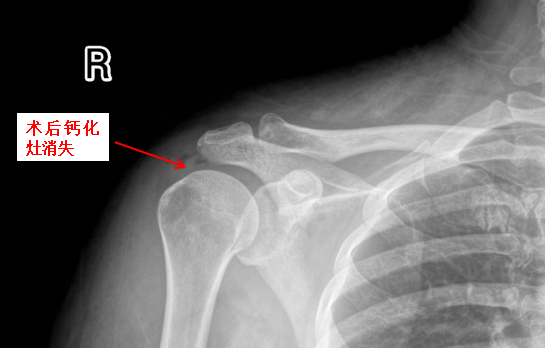

近日,年近六旬的黄阿姨无明显诱因下骤发右侧肩痛两天,夜间痛到无法入睡,止痛药仅可缓解三四小时,又再发持续剧痛,而且伴有右肩活动障碍,稍微活动一下右肩,愈加钻心疼痛来袭。饱受折磨的黄阿姨到桂林医科大学第二附属医院运动医学科门诊就诊,副主任医师谢小军一听病史,初步怀疑钙化性肌腱炎,通过初步拍X线,果真病因是它。

这种疾病名为肩关节钙化性肌腱炎,肩关节钙化性肌腱炎是肩部肌腱内钙盐异常沉积引发的炎症性疾病,常见于40-50岁人群,以肩部剧烈疼痛、活动受限为主要表现。钙化性肌腱炎是肌腱组织内出现羟基磷灰石晶体沉积的病理状态,肩袖肌腱(尤其是冈上肌腱)最常受累。钙盐沉积可能与肌腱局部缺氧、代谢异常或退行性变有关,导致炎症反应和机械性刺激,引发疼痛和活动障碍。急性期疼痛剧烈,夜间加重,可能放射至上臂;抬手、外展或旋转动作困难,严重时影响穿衣、梳头等日常活动。肩峰下或肱骨大结节处压痛,部分患者伴局部肿胀。若钙化灶>1.5cm,往往需关节镜手术治疗。

门诊医生立即为黄阿姨办理了住院,并于当天晚上完成急诊手术,通过3个0.5cm小切口在关节镜下解决了病因。镜下可见冈上肌腱内冒出牙膏状钙化沉积物,彻底清理后缝合肩袖破口。

术后当晚黄阿姨睡了一个好觉,术后右肩再无疼痛,对我们的治疗非常满意。黄阿姨打趣说术前当天戴着痛苦面具住院了,术后2天喜笑颜开出院了。